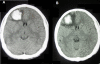

Case presentation: A 20 years old man presented with fever, myalgias, arthralgias, retro-orbital pain, vomiting and gum bleeding during a large dengue outbreak in Lahore, Pakistan. On 7th day of illness patient became afebrile, but he developed severe headaches, unconsciousness followed by altered behavior. On 9th day of illness patient developed painful neck swelling accompanied by fever, tremors, palpitations, hoarseness of voice and odynophagia. Examination revealed acutely swollen, tender thyroid gland along with features of hyperthyroidism. Laboratory evaluation revealed stable hematocrit, thrombocytopenia and leukopenia. Patient had seroconverted for anti-dengue IgM antibodies on the 10th day of illness. A non-contrast Computed Tomogram (CT) of the brain showed right frontal lobe hematoma. Thyroid profile showed increased free T3 and T4 and low TSH. Technetium thyroid scan showed reduced tracer uptake. He was diagnosed as having subacute thyroiditis and treated with oral prednisolone and propranolol. Follow up CT brain showed resolving hematoma. Patient's recovery was uneventful.